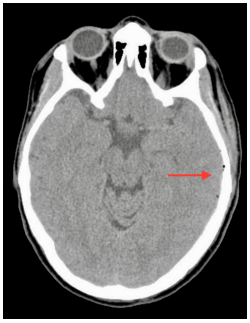

The patient returned to the emergency department with complaints of a sudden strong left parieto-temporal headache, confusion and blurred vision 25 days after the traumatic event. A cranial CT scan showed complete resolution of the SDH and pneumocephaly (Figure 3). Even though the intracranial lesions had had a natural evolution, the patient was still symptomatic and now presented with an altered state of consciousness (GCS 13 - E3M6V4). Thus, a CT venogram was performed, which identified an absence of contrast enhancement on the left distal third of transverse (Figure 4A) and sigmoid (Figure 4B) sinus and on the left internal jugular vein, compatible with DST (Figure 4C & 4D). The patient immediately started anticoagulation therapy with enoxaparin 80 mg twice a day for 4 days and warfarin for 1 year. Recently, at the 14-month follow-up, a complete dissolution of the thrombus and dural sinus recanalization were identified in the CT venogram. Genetic or acquired thrombophilia, vasculitis, and neoplastic disease were excluded.

Figure 3CT Scan preformed 25 days after TBI showing total reabsorption of pneumocephaly and complete resolution of the SDH